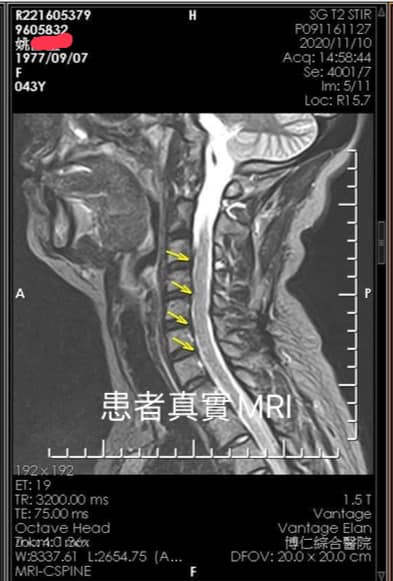

Cervical Spine Treatment Cases 頸椎治療案例 頸椎壓迫竟導致自律神經失調?耳鳴、心悸、暴瘦全因筋膜失衡! 2021.02.18 頸椎壓迫神經根導致工作受限?非手術微創療法改善關鍵公開 2021.02.17 頸椎脊髓壓迫五大症狀公開!你也有雙腳沉重、手腳麻電感嗎? 2021.01.15 長期頭痛吃藥沒效?小心你可能是「頸源性頭痛」患者 2021.01.07 #感謝新北市蘆洲區楊先生熱情見證 #頸椎病變引起肩膀痠痛無法睡眠 #曾經大痛到想立刻... 2020.12.31 #感謝新北三重劉小姐熱情見證 #神經根型頸椎病經典案例 #曾經手麻痛到無法騎摩托車 #... 2020.12.25 #遠從台東縣的熱情見證 #五個多小時的車程三百多公里很辛苦 #疼痛超過兩年打過頸椎三... 2020.12.24 #頸椎酸痛到無法睡覺是怎們回事 #醫學中心證實頸椎間盤突出 #神外醫師建議開刀但患者... 2020.12.19 #頸椎曲線弧度非常重要 #頸椎嚴重壓迫有可能逆轉嗎 #肩膀疼痛到不行合併走路都無力 #... 2020.12.09 頸椎退化壓迫神經根怎麼辦?大直林小姐四週見效的中醫微創療法 2020.12.08 #特殊案例長年過敏性鼻炎 #起因居然是頸椎交感神經筋膜壓迫 #打開椎動脈循環🔄找到解... 2020.12.05 #恭喜新店陳小姐頸椎療程畢業 #神經根型卡壓醫案 #頸椎整合中醫微創療法逆轉勝 #告別... 2020.11.24 #特殊案例頸椎手術後又再度突出案例 #感謝台中劉大哥熱情見證 #親自手捏醫師娃娃公仔... 2020.11.18 #頸椎病居然會導致手快速萎縮 #脊髓型頸椎病案例 #感謝高雄王大哥熱情見證 #頸椎整合... 2020.11.13 #神經根型頸椎病讓人痛到無法入眠 #感謝新店陳小姐熱情見證 #患者的疼痛日誌讓人感動 ... 2020.11.11 ← 上一頁 3 4 5 6 7 下一頁 →